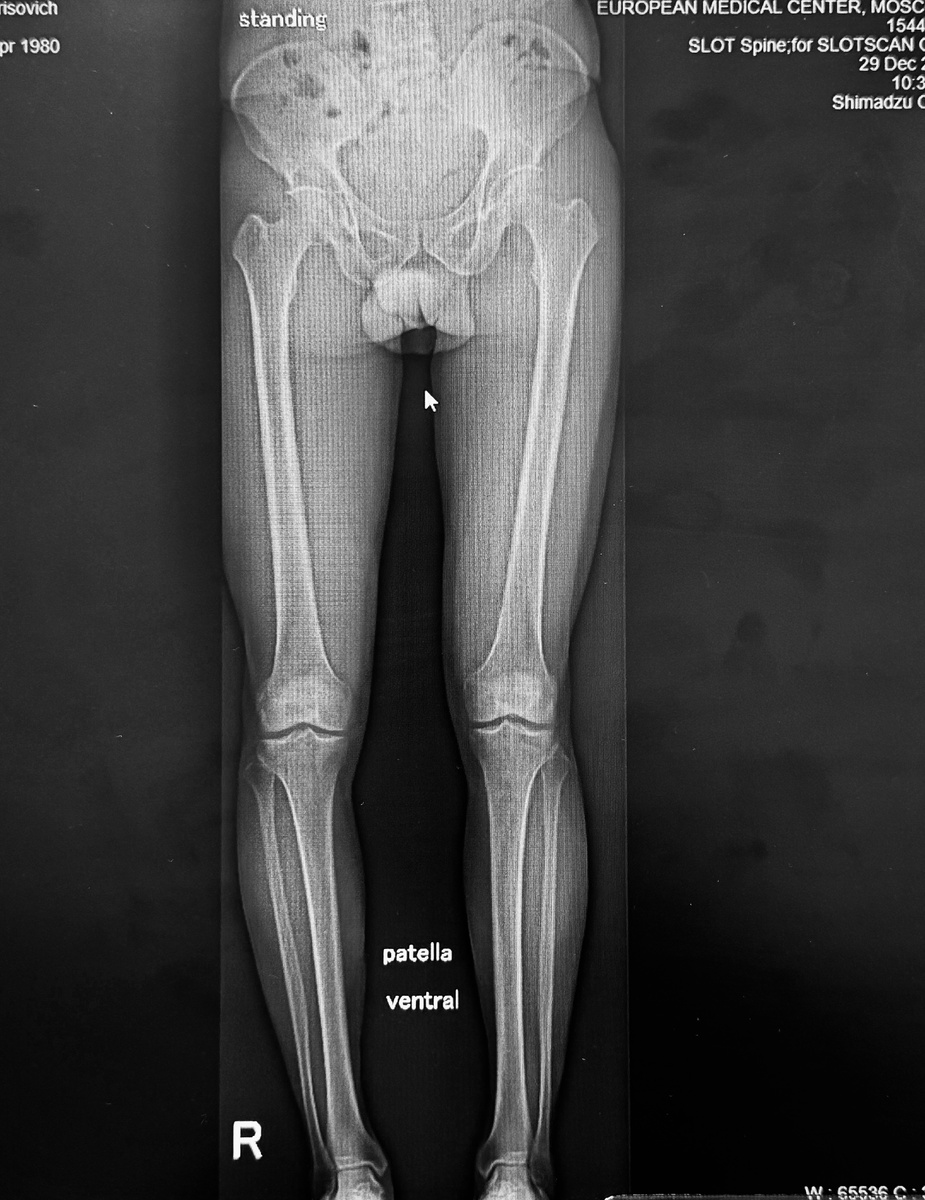

Ортопедический чекап (осмотр по-нашему) выявил интересную штуку - варусную (О-образную) деформацию той же голени, и плосковальгусную деформацию стопы той же ноги.

На снимке выше невооруженным глазом видно, что голени не параллельны: левая стоит вертикально, как и должна, а правая смещена внутрь.

Зеленая линия - правильная ось, правильное распределение нагрузки на ногу, красная - всё ровно наоборот:

Причём красная линия проходит ровно через то место, где и находился разорванный мениск! Чувствуете связь? Избыточное давление, перегрузка, разрыв. Чистая механика.

Идем выше: прямая нога - длинная, кривая - короткая. Соответственно, перекос таза и позвоночника.

Тазобедренные суставы и большие вертелы на разных уровнях. Неизбежны боли в самых разных местах, перегрузка правого тазобедренного сустава.